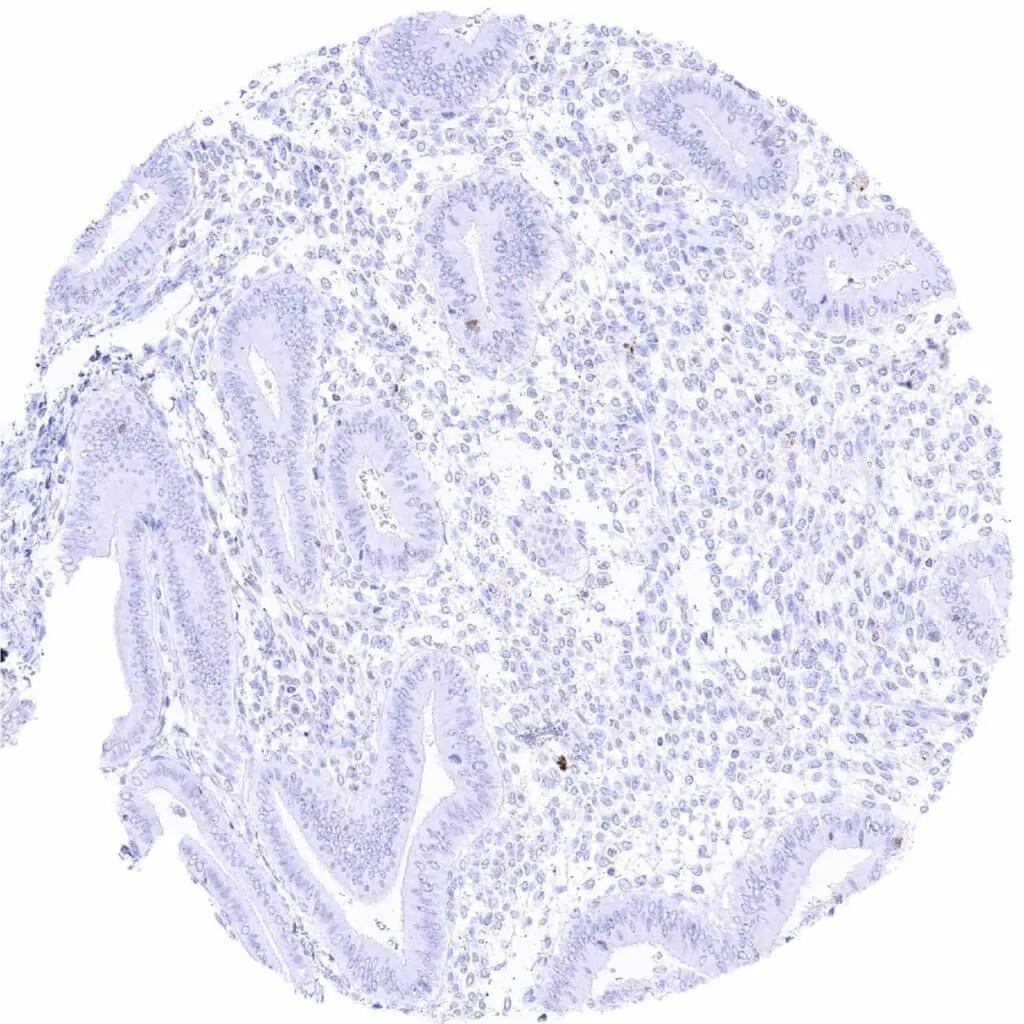

Stomach, antrum – Distinct CD38 staining of a some inflammatory cells

Stomach, corpus – Distinct CD38 staining of a some inflammatory cells